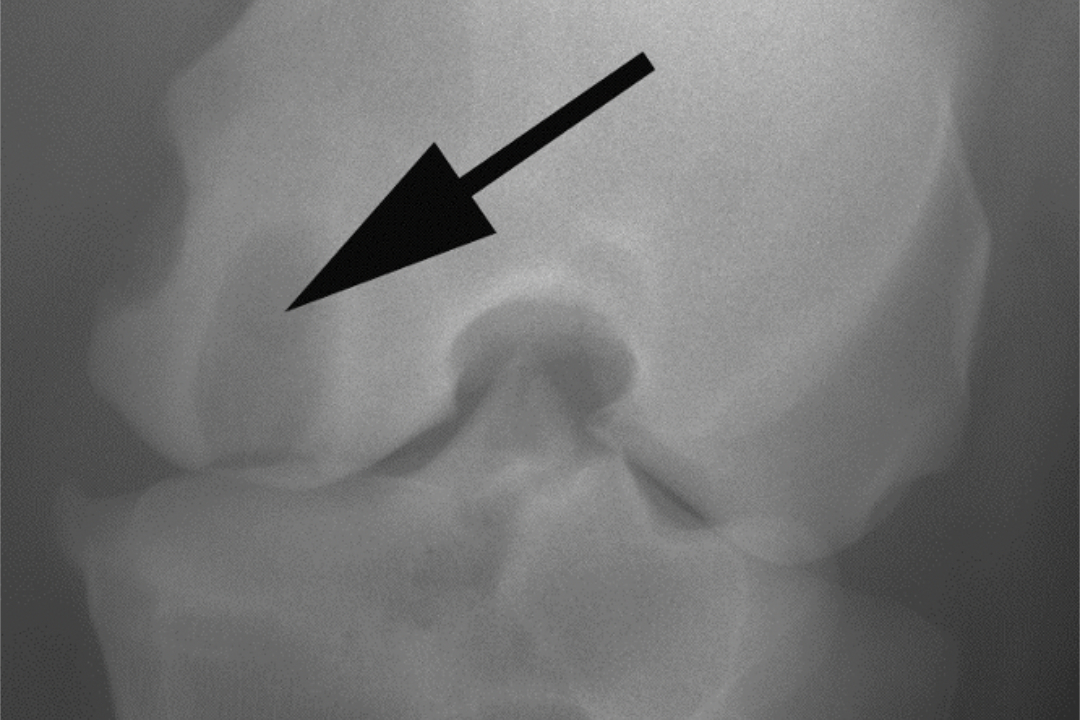

Dieses Bild zeigt ein Röntgenbild eines Pferdes mit einer Knochenzyste im medialen (Inneren) Kniegelenksbereiches.

Die Röntgendurchlässigkeit sieht man als runde bis ovale, zum Teil auch unregelmässig umrandete konturierten Aufhellung, die häufig von einer weisslichen Zone umgeben wird. Unter dem Mikroskop stellen sich die Zysten als Hohlräume im Knochen dar, die mit Flüssigkeit und Bindegewebe gefüllt sind.

Radiographisch werden runde bis ovale Aufhellungen, umgeben von einem hellen Rand, gefunden. Manchmal zeigen benachbarte Gelenke Anzeichen von Arthrose. Qualitativ hochstehende Röntgenaufnahmen können erforderlich sein, da sonst die Läsionen leicht übersehen werden. Die Grösse der Knochenzysten variiert je nach Gelenk und ist normalerweise zwischen 5 und 10 mm gross. Eine Gelenkverbindung ist nicht in allen Fällen nachweisbar, wobei kleine Verbindungen der Zysten mit dem Gelenk radiologisch nicht immer darzustellen sind.